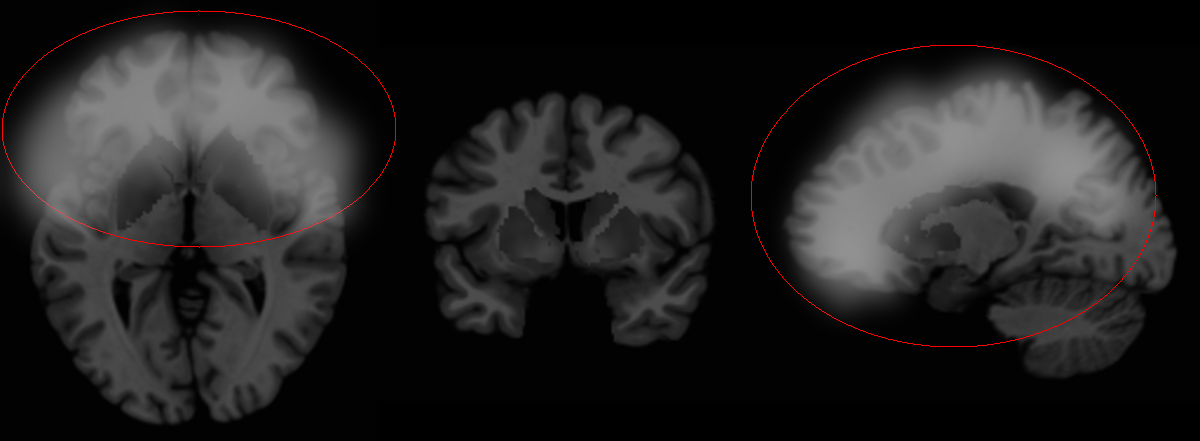

10:03 AM:最后一根电极与保护帽已置于对象头部。激活SCP-7080-7,检测到完整意识。

5:14 PM:意识测试完成。对象躺下后意识操控开始。「神显Mk. VII」开始作用于对象,启动10分钟的意识消除进程。对象失去了意识。

6:30 PM:「神显Mk. VII」开始作用于对象,启动30分钟对左脑的意识消除进程,消除程度为50%。对象报告了与上次「神显」作用相同的感觉。

7:00 PM:「神显Mk. VII」开始作用于对象,启动30分钟对右脑的意识消除进程,消除程度为50%。对象报告感到烦躁。

7:30 PM:「神显Mk. VII」开始作用于对象,启动10分钟对右脑的意识消除进程,消除程度为90%。对象报告感到迟缓,亦感到烦躁。

7:40 PM:「神显Mk. VII」开始作用于对象,启动5分钟对右脑的意识消除进程,消除程度为99%。对象进入类昏迷状态。

7:41 PM:为避免[已编辑],Joseph Locke博士要求对右脑意识增强10,000%持续5分钟,以使其恢复正常状态。然而,操控「神显Mk. VII」的助手误将其作用于左脑。对象脱离类昏迷状态后坐起。此动作导致保护帽与电极被挣脱。